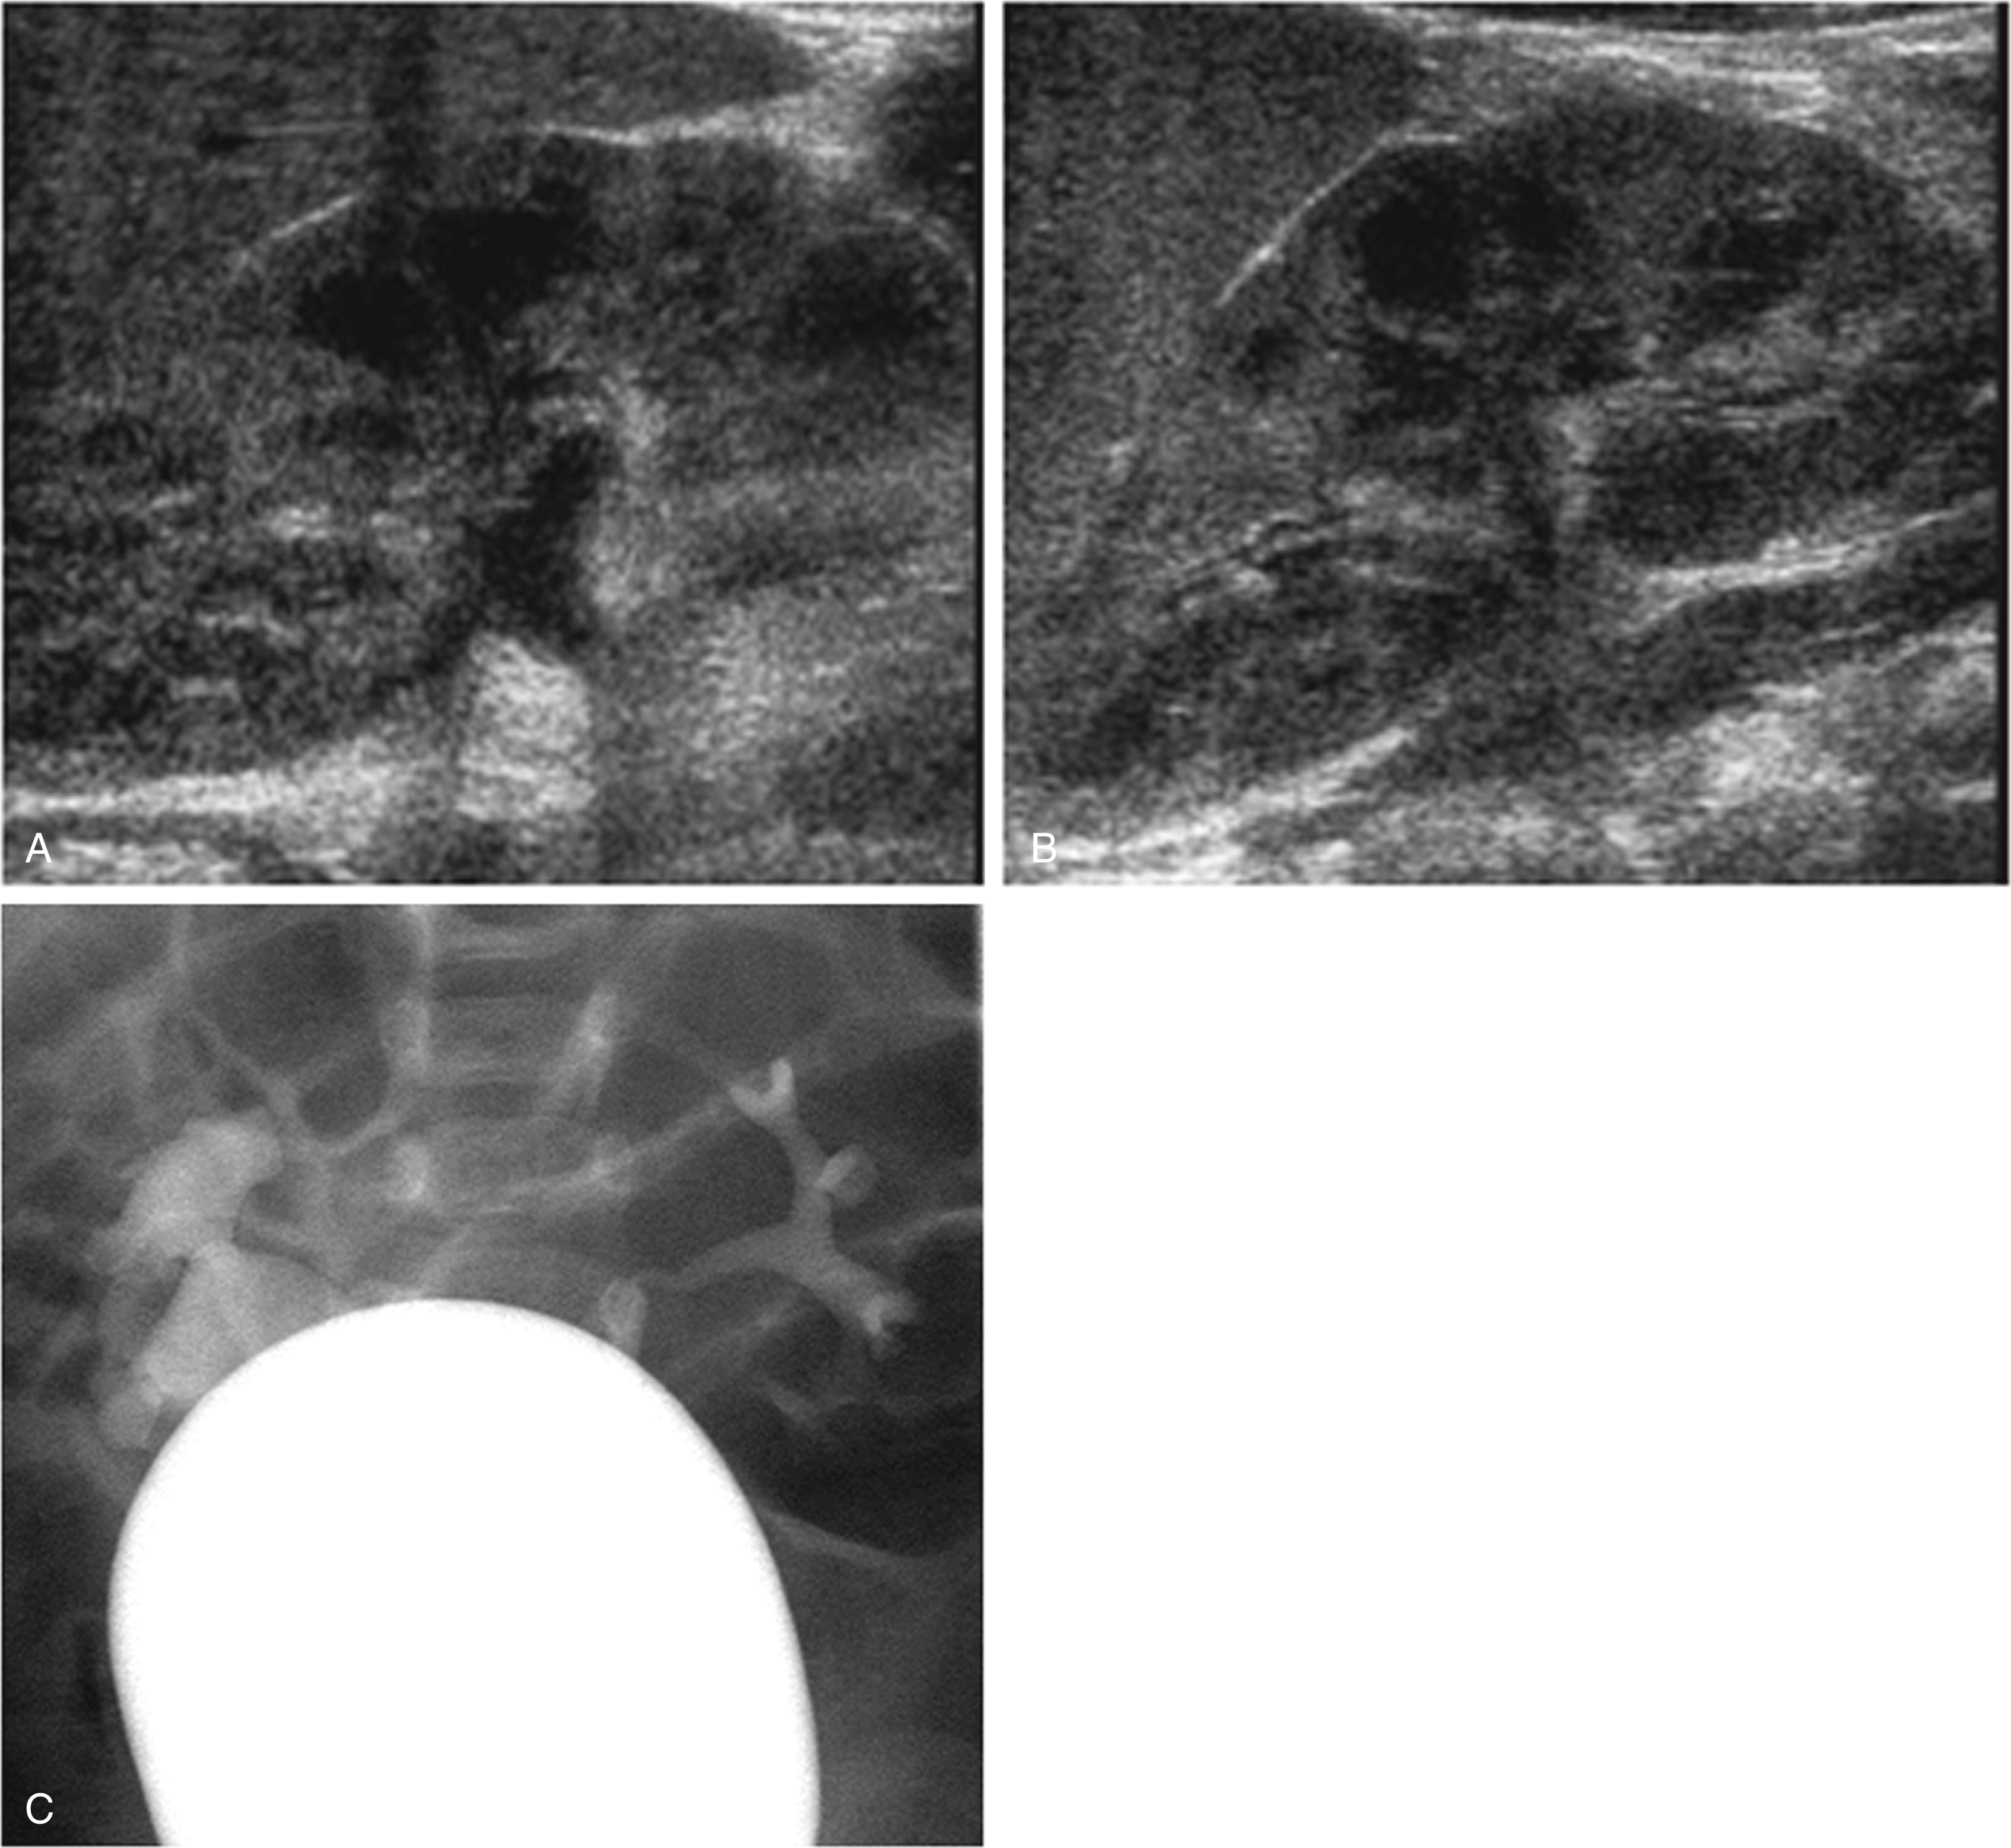

Fig. 8.6, (A–C) A normal ultrasound does not exclude reflux. Reflux is an intermittent process. Although reflux may cause urinary tract dilation, when there is no reflux, the urinary tract may appear normal. This patient had a febrile urinary tract infection. His renal and bladder ultrasound appeared normal (A, B). The voiding cystourethrogram (C) shows right grade 3 vesicoureteral reflux and left grade 2 vesicoureteral reflux.